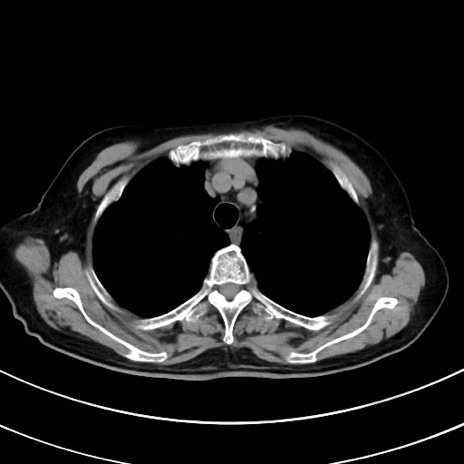

症例33(横断像)

【症例】70歳代 女性

【主訴】心窩部痛

【現病歴】延髄病変の精査・加療にて神経内科入院中。本日より心窩部痛あり。

【既往歴】虫垂炎

【身体所見】右下腹部を中心に圧痛と反跳痛あり。

【データ】WBC 10900、CRP 0.02